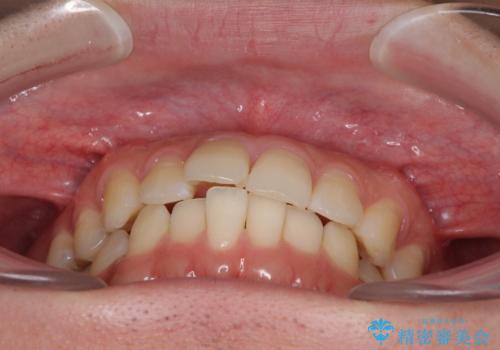

インビザライン・ライトによる矯正治療の後戻り改善

- 矯正治療の後戻りを気にして来院された患者様です。

後戻りは軽微でしたので、インビザライン・ライトにより矯正治療を行うこととしました。

再矯正後の後戻りを防ぐため、歯列排列後に、下顎前歯はワイヤーによる固定を行いました。

下顎前歯の歯列を動かないようにしておくことで、上顎前歯の後戻り防止にも効果を発揮します。